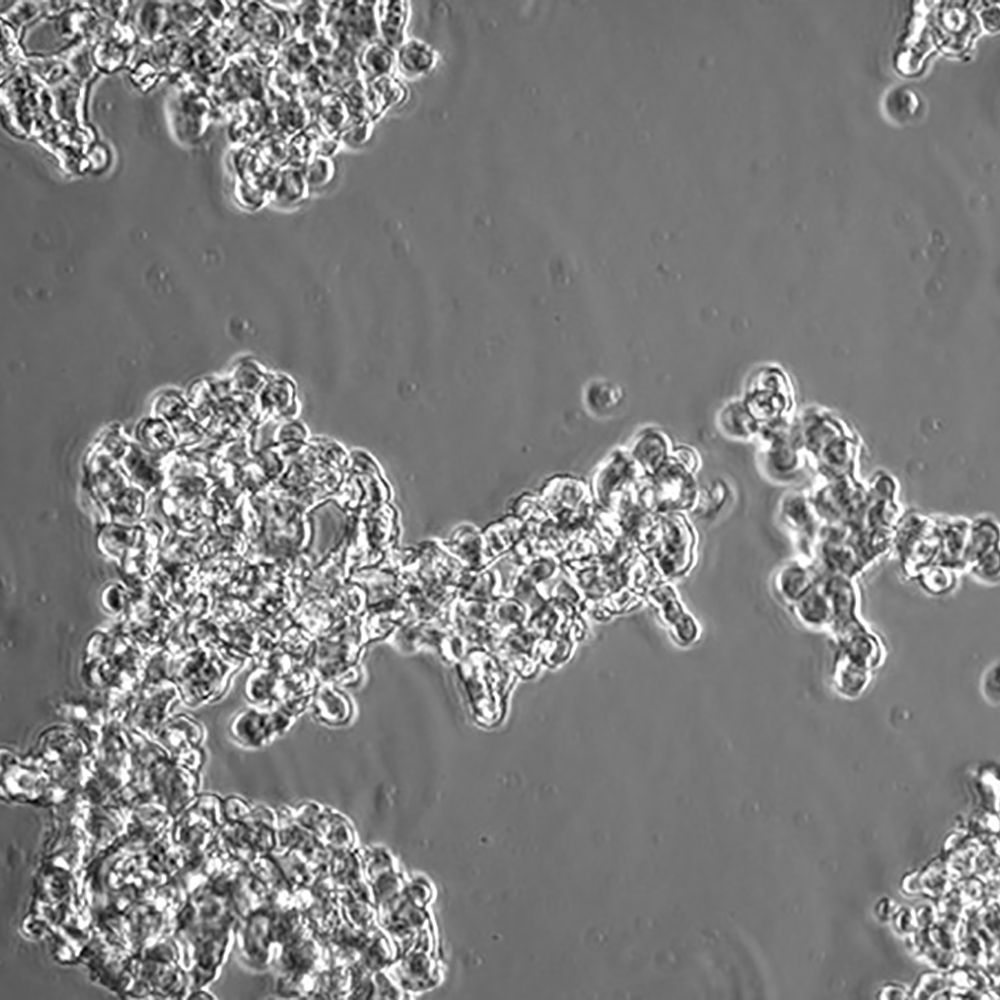

中文名稱 人小細胞肺癌細胞

組織來源 小細胞肺癌;骨髓轉移;男性

生長特性 懸浮

培養基 RPMI-1640+10%FBS+1%P/S

培養條件 Atmosphere: Air, 95%; CO2, 5%。Temperature: 37℃

細胞傳代步驟 如果細胞密度達80%-90%,即可進行傳代培養。1. 棄去培養上清,用不含鈣、鎂離子的PBS潤洗細胞1-2次。2. 加2ml消化液(0.25%Trypsin-0.53mM EDTA)于培養瓶中,置于37℃培養箱中消化1-2分鐘,然后在顯微鏡下觀察細胞消化情況,若細胞大部分變圓并脫落,迅速拿回操作臺,輕敲幾下培養瓶后加少量培養基終止消化。3. 按6-8ml/瓶補加培養基,輕輕打勻后吸出,在1000RPM條件下離心4分鐘,棄去上清液,補加1-2mL培養液后吹勻。4. 將細胞懸液按1:2到1:5的比例分到新的含8ml培養基的新皿中或者瓶中。